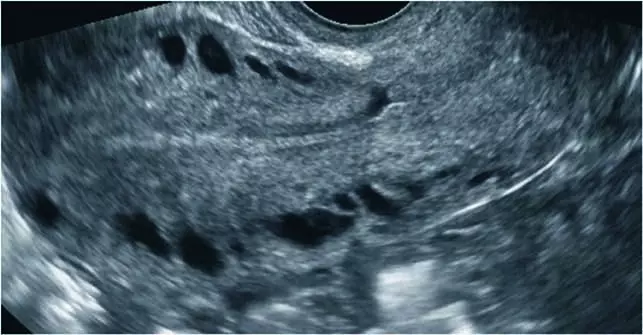

Po ok. 3 miesiącach występowania dolegliwości pacjentka zgłosiła się do lekarza rodzinnego, który po wykonaniu badań podstawowych [morfologia, CRP (ang. C reactive protein), parametry życiowe – wszystkie w normie], ze względu na opisywany związek dolegliwości z cyklem miesiączkowym i współżyciem zalecił konsultację ginekologiczną. W badaniu dwuręcznym stwierdzono niewielką tkliwość przydatków i macicy, we wziernikach obecność obfitej, niezapalnej wydzieliny w pochwie, pH 4.0. Lekarz ginekolog wykonał również ultrasonograficzne (USG) badanie przezpochwowe, nie stwierdzając nieprawidłowości. Podejrzewając zapalenie przydatków, zalecił antybiotykoterapię i dalsze konsultacje w przypadku braku poprawy. Antybiotykoterapia nie zmniejszyła dolegliwości bólowych, pacjentka była również konsultowana przez chirurgów i gastrologów, wykonano USG jamy brzusznej oraz komplet badań biochemicznych, nie zdiagnozowano przyczyny bólu. W czasie procesu diagnostycznego podejmowano próby leczenia empirycznego za pomocą doustnej antykoncepcji hormonalnej, leków rozkurczowych, niesterydowych leków przeciwzapalnych i antybiotyków – bez pozytywnego efektu. W trakcie kolejnej konsultacji ginekologicznej, ze względu na podejrzenie endometriozy, pacjentce zaproponowano laparoskopię diagnostyczną, w trakcie której nie stwierdzono nieprawidłowości. Wobec niestwierdzenia patologii mogącej tłumaczyć objawy poinformowano pacjentkę o możliwości rozważenia histerektomii z przydatkami bądź próby rozważenia zaakceptowania dolegliwości. Ostatecznie, po ok. 1,5 roku od wystąpienia pierwszych objawów, pacjentka trafiła na konsultację do III Kliniki Ginekologii. W trakcie ponownego przezpochwowego badania USG uwagę zwróciły następujące znaleziska: liczne poszerzone naczynia żylne w obrębie myometrium (ryc. 1) oraz poszerzone naczynie żylne w okolicy lewych przydatków – żyła jajnikowa lewa (ryc. 2). Po uciśnięciu sondą pacjentka podawała jedynie nieznaczne dolegliwości w okolicy lewego jajnika, natomiast bardzo żywo reagowała bólowo przy ucisku okolicy poszerzonego naczynia. W badaniu dopplerowskim w poszerzonej żyle jajnikowej stwierdzono nieprawidłowy, wahadłowy przepływ (ryc. 3). Na podstawie obrazu USG wysunięto podejrzenie zespołu PCS. W kolejnym etapie diagnostyki wykonano badanie rezonansu magnetycznego z opcją naczyniową, w którym stwierdzono znaczne poszerzenie splotów żylnych przymacicz oraz żyły jajnikowej lewej, potwierdzając rozpoznanie PCS.

Ryc. 2. W przezpochwowym badaniu USG stwierdzono poszerzoną żyłę jajnikową lewą do 10,4 mm